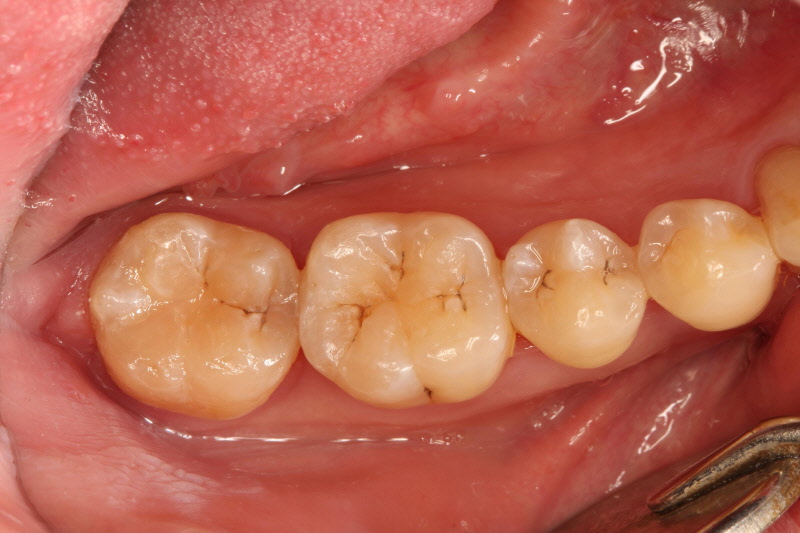

좌측의 초기부터 점점 진행되는 충치의 사례입니다. 제일 좌측은 치료받지 않고 두어도 무관한 정도이지만 가장 우측은 발치를 시행해야 하는 정도로 진행되어 있습니다. 충치는 명쾌하게 단계를 자를 수 있는 병이 아닌 점진적 진행으로 나타나므로 같은 정도의 충치라도 많은 변수를 고려해야 합니다. 의사마다 치료 방법과 방향이 다른 이유입니다. 각자의 경험과 생각하는 바, 앞으로의 예후와 환자의 조건들을 총 취합해서 평가해야 하니 같은 경우는 드물게 됩니다 .

치아우식증의 치료는 진행 단계에 따라 다르지만 원리는 비슷합니다. 치아우식증에 이환된 부위를 제거하고 그 부위를 채워 회복하며 나머지 남아있는 자기 치아 부위를 파절이나 손상으로부터 보호하는 것입니다. 충치를 치료하는데 있어서는 두 가지를 생각해야 합니다. 채워 넣는 부분의 수명과 남아있는 나머지 자신의 치아부위의 수명을 동시에 고려해야 합니다. 흔히들 채워 넣는 수복물의 수명만 많이 고려하지만, 결국 그 수복물을 유지해주는 것은 잔존 치아 부분입니다. 잔존 치아 부위에 무리를 가하는 수복물이라면 치료 수명은 오래가지 못할 것입니다.